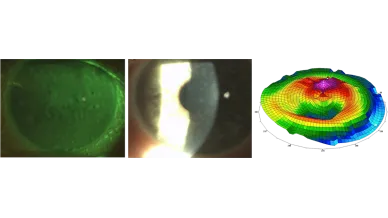

Orthokeratologie-Seminar

Natascha Wohler, Jana Herzner, Manuel Kretz

990,00€ Mehr Infos